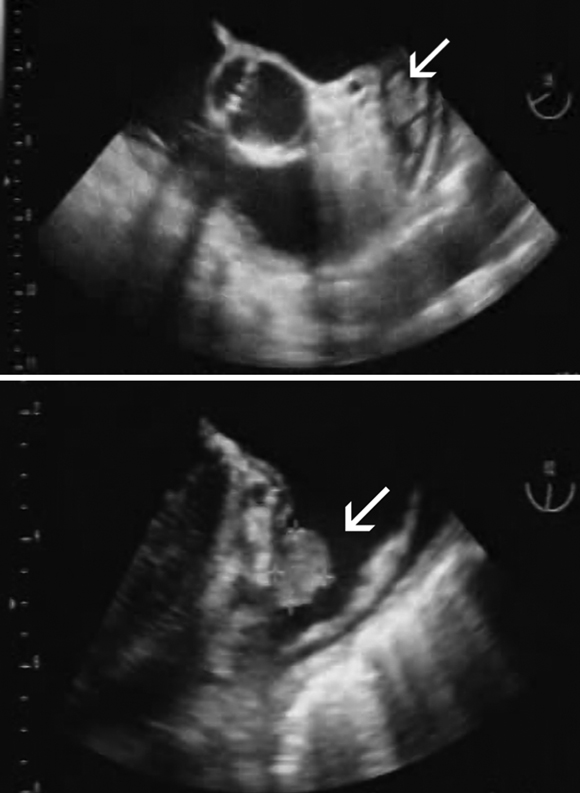

AF predisposes to the formation of blood clots within the left atrium (LA) and particularly the left atrial appendage (LAA) (Box 3), and these may embolise to the systemic circulation. Consequently, AF is an independent risk factor for cardioembolic ischaemic stroke. Although most strokes in people with AF are embolic from the LA/LAA, about a quarter may originate elsewhere — from the left ventricle, heart valves, and extracranial and intracranial arteries. Cardioembolic strokes in patients with AF are typically larger, associated with higher early mortality, and occur in older patients compared with strokes in patients with sinus rhythm (Box 4).

We gratefully acknowledge the assistance of Dr Andy Yong for providing the transoesophageal echo image of a left atrial appendage thrombus.